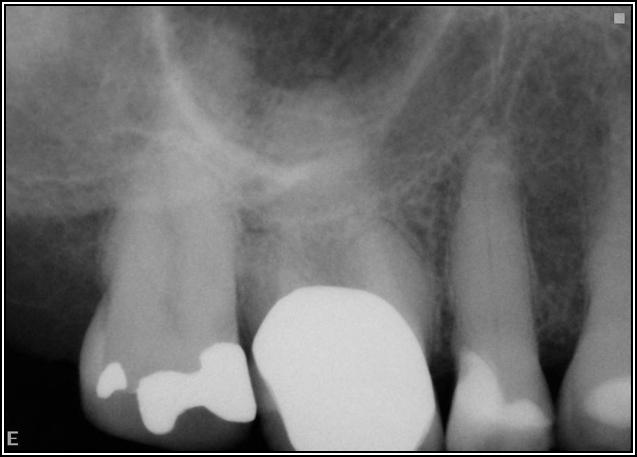

Occlusion is one of the most overlooked areas in endodontics; however, other than remaining structure, it is the most important factor.7 Patients who are heavy bruxers can cause the need for a root canal from the lateral forces. Patients who clench pose a different challenge with apical forces, yet the damage from both can be the same. Figure 7 shows a patient with bruxism. The patient had pain in response to hot and cold stimulus, and the clinicians needed a bitewing to determine which tooth was causing the pain. From the periapical (PA), it was clear that tooth No. 2 had a large problem, No. 3 had a crown, and No. 4 had a large restoration. Any of the three may have been the source of the problem.

With the bitewing shown in Figure 8, it became clear there was gross decay in tooth No. 3 that could not be seen on the PA, and there was a periodontal defect, a pulp stone, in No. 2. There was also a class V lesion revealing the bruxism, flat occlusion, multiple restorations in No. 30, a post in No. 31, and decay on No. 2 as well. The post in No. 31 was useless because when a post is placed, it must be the right length, width, and size. If the post is too short, there will be a greater fulcrum and the tooth will break. If it is too long, the clinician can break it by wedging it. If it is too short, it will not hurt the tooth, but it will not provide any valuable function. It is overall preferable to do posts in teeth having just single restorations rather than abutments for bridges because those teeth are already under greater force. If the technique is not performed correctly, iatrogenic issues may result.

Fig 7. Bruxism.

Figure 7

Fig 8. Bitewing revealed decay and other problems.

Figure 8